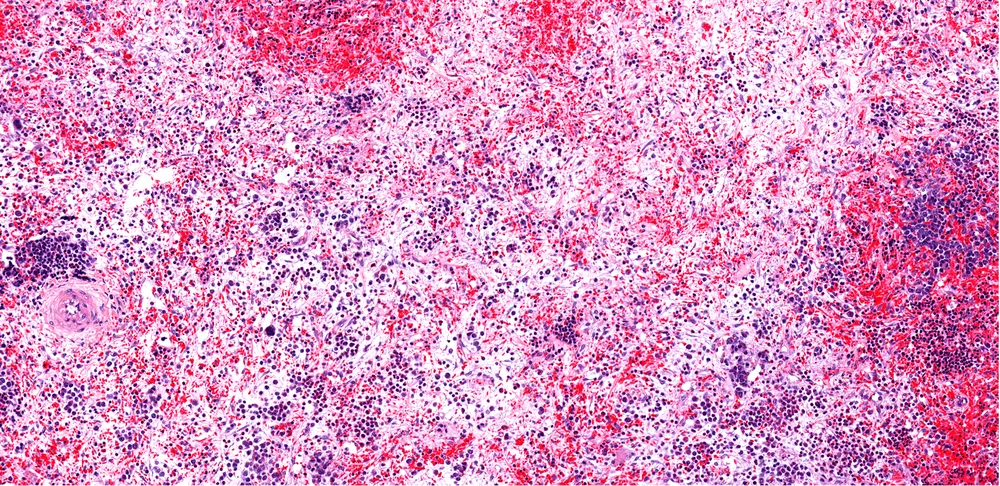

It's diagnosed through a bone marrow biopsy, which helps doctors see how much fibrosis is there, and they grade it from 0–3 depending on the severity of the fibrosis.

- Certain cell types and cell sizes present in your bone marrow